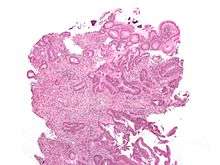

Cancer — Invasive adenocarcinoma (the most common type of colorectal cancer). The cancerous cells are seen in the center and at the bottom right of the image (blue). Near normal colon-lining cells are seen at the top right of the image.

Adenocarcinoma is a malignant epithelial tumor, originating from superficial glandular epithelial cells lining the colon and rectum. It invades the wall, infiltrating the muscularis mucosae layer, the submucosa, and then the muscularis propria. Tumor cells describe irregular tubular structures, harboring pluristratification, multiple lumens, reduced stroma ("back to back" aspect). Sometimes, tumor cells are discohesive and secrete mucus, which invades the interstitium producing large pools of mucus/colloid (optically "empty" spaces). This occurs in mucinous (colloid) adenocarcinoma, in which cells are poorly differentiated. If the mucus remains inside the tumor cell, it pushes the nucleus at the periphery. This occurs in "signet-ring cell." Depending on glandular architecture, cellular pleomorphism, and mucosecretion of the predominant pattern, adenocarcinoma may present three degrees of differentiation: well, moderately, and poorly differentiated.[55]